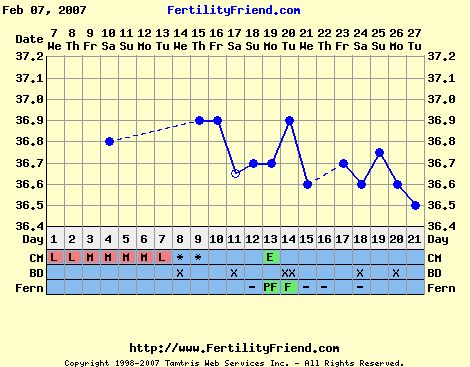

Málna!

Sajnálom,hogy nem jött össze a hónap.Mindenesetre,az már jó jel,hogy volt egy halvány 2 csíkos teszt.Remélhetőleg köv.hónapban erős két csík lesz.